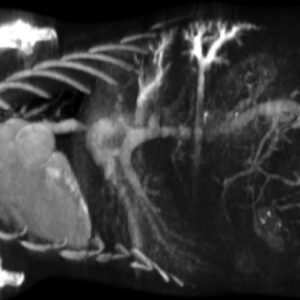

Preclinical Imaging Validation

Imaging studies demonstrate clear opacification of liver lobes and metastases in murine models following a single injection. Longitudinal monitoring confirms sustained enhancement suitable for quantitative assessment of lesion progression and therapeutic response.

Following administration, ExiTron™ nano 6000 accumulates in liver parenchyma, producing high contrast between healthy tissue and surrounding structures. This contrast facilitates clear identification of liver tumors and metastatic lesions, supports quantitative measurement of tumor burden, and enables monitoring of morphological changes over time. The low injection volume and favorable cardiovascular tolerability make the agent suitable for animals with limited physiological reserve.

Conventional CT contrast agents often provide transient liver enhancement, limiting assessment of chronic or progressive hepatic conditions. ExiTron™ nano 6000 addresses this limitation through prolonged retention in healthy liver tissue, allowing repeated imaging sessions without additional contrast administration. The agent also provides strong enhancement of spleen tissue, supporting comprehensive assessment of the reticuloendothelial system.